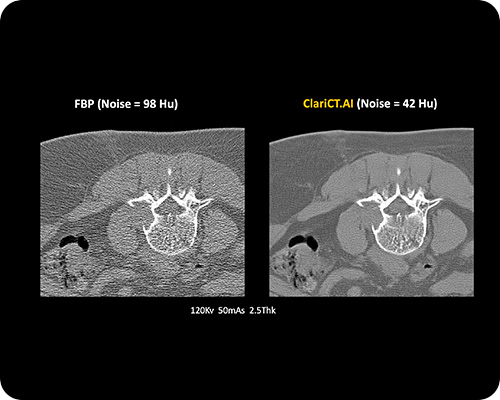

ClariCT.AI 의 전례없는 이미지 선명도

노이즈 제거 전후

전 후